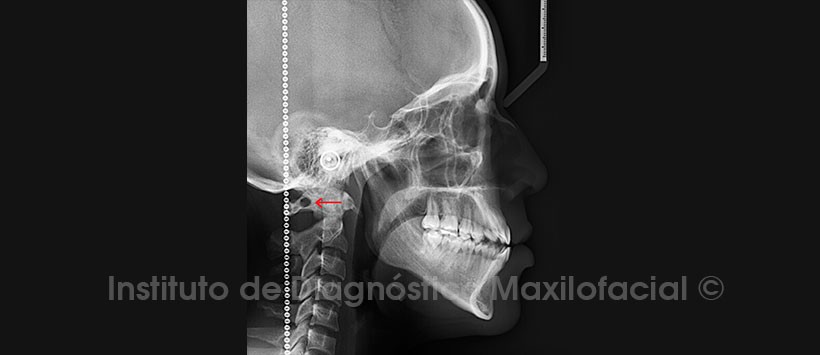

En la radiografía lateral (Figura 2), en la región cervical, en el arco posterior de la vértebra Atlas (C1), se puede apreciar una osificación anómala en forma de puente, que delimita un foramen.

En el estudio mediante tomografía computarizada de haz cónico (CBCT), en las reconstrucciones 3D, se evidencia claramente la alteración antes descrita y su relación con estructuras adyacentes, además donde podemos afirmar que dicha osificación se ha dado de manera completa y en ambos lados, dando origen a lo que se conoce como Ponticulus posticus bilateral. (Figuras 3, 4 y 5)

El Ponticulus posticus es un puente óseo situado en el arco posterior del atlas en relación con el paso de la arteria vertebral. Su presencia se ha asociado con el desarrollo de dolor cervical y trastornos cerebrovasculares. Es arco óseo que conecta el tubérculo retro glenoideo situado por detrás de la fosa articular superior del atlas con su arco posterior. Este elemento ha sido descrito en la literatura clásica como una variación anatómica que se origina en la osificación del segmento lateral del ligamento atlanto-occipital posterior o la cápsula de esta articulación. Su importancia radica en la relación que se establece con la arteria vertebral, la cual, después de salir del agujero transverso de la vértebra atlas, transcurre en su arco posterior y por el agujero generalmente en busca de la membrana fibroósea atlanto-occipital posterior, que se perfora para entrar en el canal vertebral. Este puente óseo ha sido llamado por diferentes nombres, tales como foramen sagittale, foramen posterior atlantal; foramen arcuato , una variante de la anomalía de Kimmerle, foramen retro articular superior, canalis vertebralis, anillo de la arteria vertebral retro articular y anillo de la arteria vertebral retro-condilar. Sin embargo, su nombre más aceptado es el derivado del latín Ponticulus posticus (pequeño puente posterior).

Radiográficamente, se detecta en la proyección lateral de columna cervical, se puede observar como un anillo óseo. La presentación de estos arcos óseos o puentes óseos puede ser unilateral o bilateral y se puede clasificar en tres tipos: